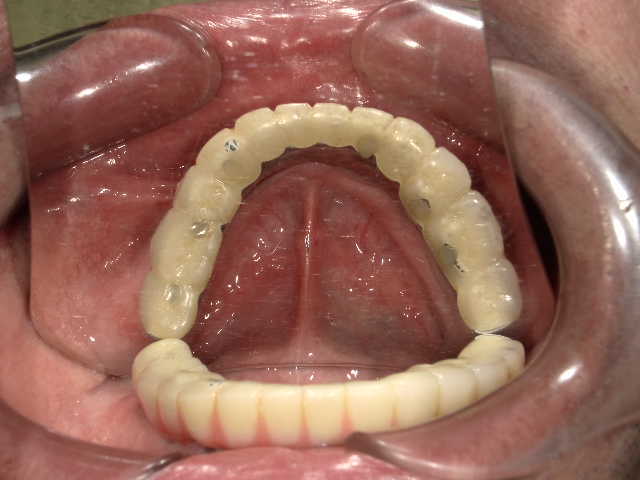

冨田先生についてCASE01 All on 4

下の歯は4本、上の歯は5本インプラントを埋め込み、上下ともに1日で歯をセットしました。上の歯に関しては、単に5本埋入すればいいという問題ではありません。

- コメント

下の歯は4本、上の歯は5本インプラントを埋め込み、上下ともに1日で歯をセットしました。上の歯に関しては、単に5本埋入すればいいという問題ではありません。鼻の下の硬い骨を使ったり、ガミースマイル(=歯茎が見えてしまう笑顔)改善のために骨を削ったりする必要があります。また、下の歯は神経麻痺を回避するためにオトガイ孔(下の神経の出口)にプローブ(=先端の細い専用の器具)を挿入したりと細かなケアが大切です。

また、歯の治療をしてもどうしても歯を残すことが難しい状態に対しても、インプラントを埋めこむと同時に抜歯をすることで、All on 4の治療が可能になります。手術をしたその日のうちに仮歯が入るため、すぐに固定式の歯が必要だというような人にも向いている治療法です。